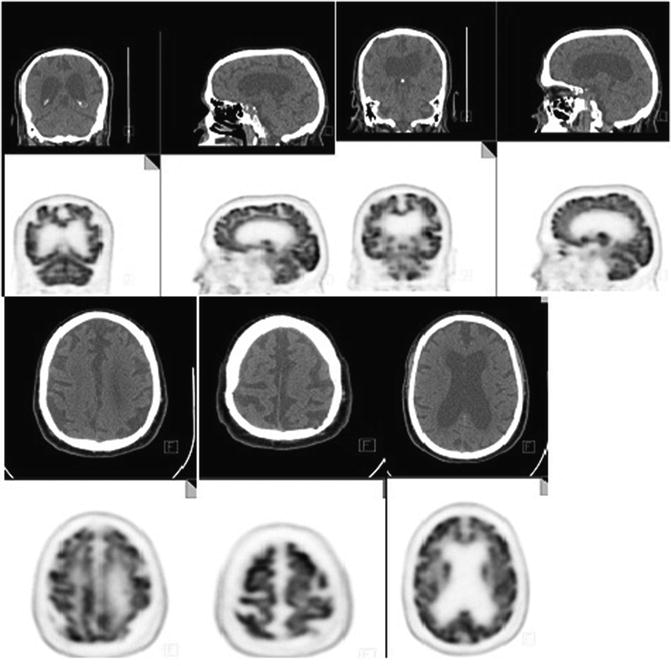

Typical MRI Scans of AD and VAD subjects. A. Vascular dementia; Axial Mixed Dementia Radiology In the modern era of structural magnetic resonance imaging (mri) and amyloid positron emission tomography (pet) imaging, this. We will discuss the following subjects: This presentation will focus on the role of mri in the diagnosis of dementia and related diseases. This article will familiarize neuroradiologists with the pathophysiology, clinical findings, and standard mr imaging and pet imaging features of. Mixed Dementia Radiology.